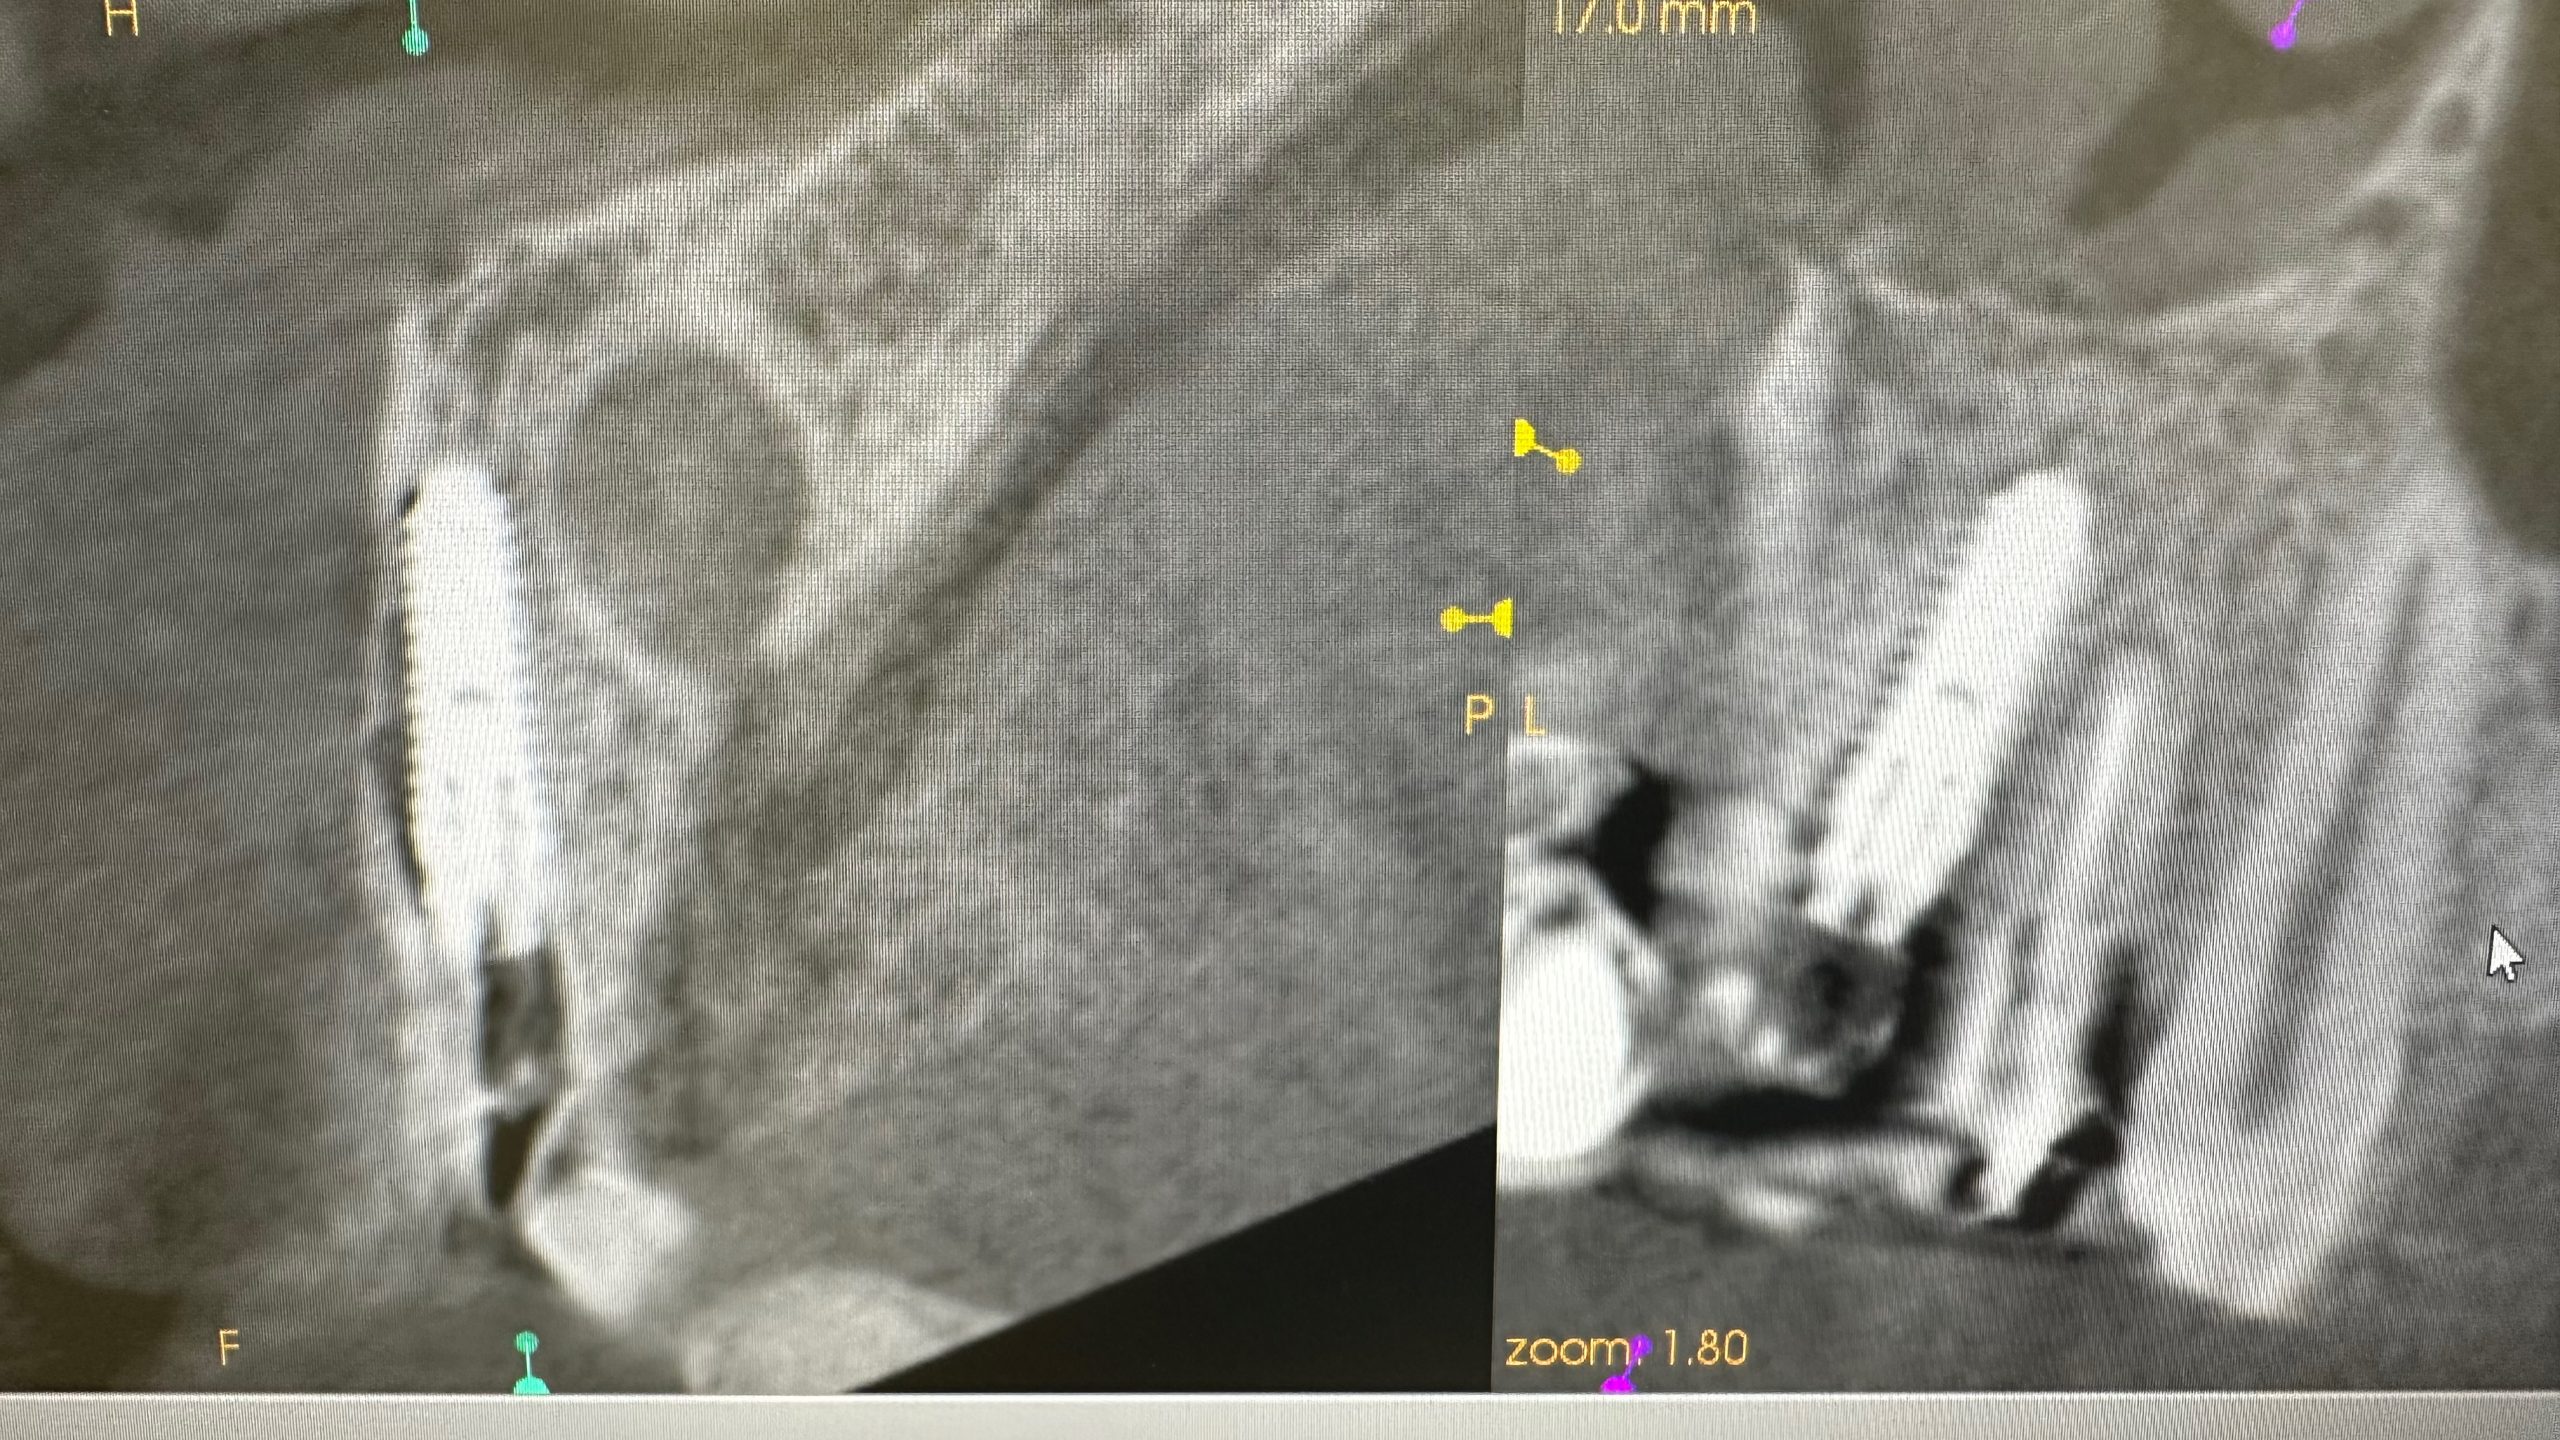

土曜日朝、前歯の抜歯即時

切歯管が近接しているから慎重にがテーマ!

その前に、部分抜歯し唇側束状骨の吸収を防ぐ!

色々な名称あり、ソケットシールドやらルートメンブレンやら他もあり